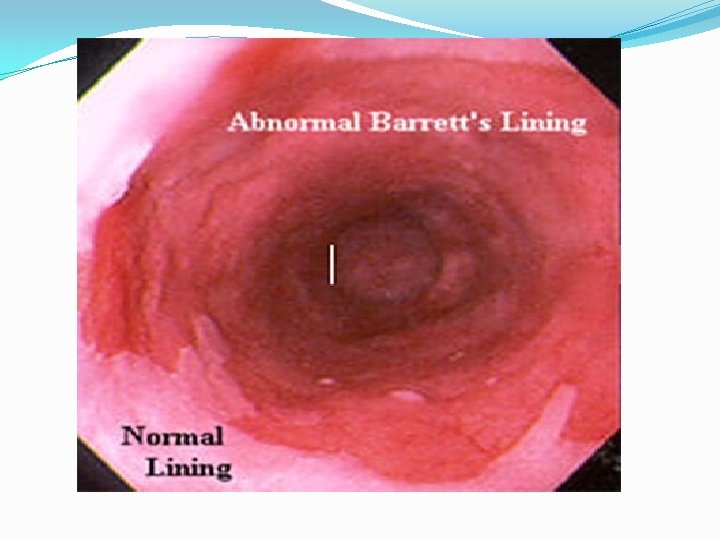

4. Endoscopy : allows diagnosis of erosive esophagitis and complications such as strictures or Barrett esophagus; biopsies can be taken. 5. Laryngotracheobronchoscopy : posterior laryngeal inflammation and vocal cord nodules. 6. Empirical antireflux therapy

Complications of GERD 1. Esophageal *Esophagitis and Stricture. * Barrett Esophagus *Adenocarcinoma 2. Nutritional: failure to thrive because of caloric deficits.